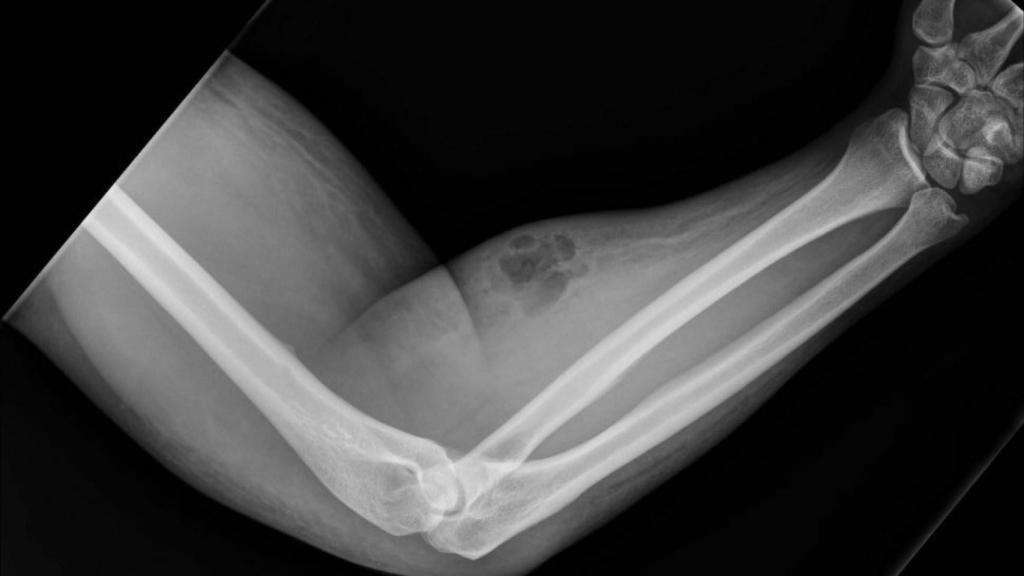

La radiografía del bulto en el brazo del paciente. Dunne et al (Irish Medical Journal)

Su paciente, un hombre de 33 años, había acudido a consulta para tratar el dolor que sufría en la zona renal después de levantar un objeto pesado tres días antes. El joven presentaba un historial crónico de dolores en la espalda baja de tipo no neuropático. La sorpresa para los especialistas vino cuando, durante la exploración de sus extremidades superiores, se toparon con una lesión papuloeritematosa en su antebrazo.

¿Qué había provocado la hinchazón? A las preguntas de los médicos, el hombre confesó que se había estado inyectando su propio semen mediante una aguja hipodérmica que había comprado online como método autoprescrito contra el dolor. Se había practicado una inyección mensual durante el último año y medio, pero estaba sufriendo tanto en aquél momento que había decidido forzar la "dosis" y practicarse tres pinchazos, intravasculares e intramusculares.

La infiltración de líquido seminal le había provocado una infección bacteriana que fue tratada con antibióticos. Además, los repetidos pinchazos buscado la vena habían provocado edemas llenos de fluido, hinchazón e inflamación, y la dermis exterior presentaba dureza. Durante la estancia hospitalaria, su dolor de espalda remitió, explican los autores, y el paciente optó por marcharse a casa declinando la posibilidad de que le drenasen mediante una incisión su particular absceso.